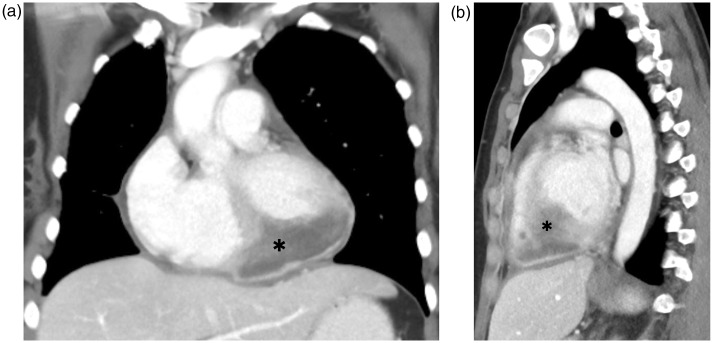

我们报告一例33岁的妇女因呼吸困难和发烧而紧急入院。病史包括完全缓解的宫颈鳞状细胞癌。胸部增强计算机断层扫描(CT)显示浸润性心脏肿块,表明可以排除肺炎。通过超声心动图和心脏磁共振成像(MRI)进一步评估肿瘤显示经壁浸润的顶室间隔,肿块延伸到左、右心室腔。这个肿块高度怀疑是心脏转移。宫颈癌引起的心脏转移极为罕见。复发的宫颈癌累及心脏应考虑,即使在治疗方法。无创成像在心脏肿块的检查中起着至关重要的作用。超声心动图、CT和MRI是心脏内病变完整检查的互补成像方式。

We report a case of a 33-year-old woman with emergency admission due to dyspnoea and fever. History included squamous cell carcinoma of the cervix in complete remission. Contrast-enhanced computed tomography (CT) scanning of the chest, which was indicated to rule out pneumonia, revealed an infiltrative cardiac mass. Further assessment of the tumour by echocardiography and cardiac magnetic resonance imaging (MRI) showed transmural infiltration of the apical interventricular septum with a mass extending into the left and right ventricle cavities. The mass was highly suspicious for a cardiac metastasis. Cardiac metastases from cervical cancer are extremely rare. Recurrence of cervical carcinoma involving the heart should be considered even after a curative therapy approach. Non-invasive imaging plays a paramount role in investigating cardiac masses. Echocardiography, CT and MRI are complementary imaging modalities for complete work-up of intracardiac lesions.